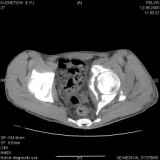

Уважаемые коллеги! Хотелось бы услышать совет по тактике лечения представлленого больного.Поступил после лечения в одном изотделений области. Травма 2,5 месяца назад. После выведенияиз шока был произведен остеосинтез перелома бедра, предплечья, до перевода к нам проводилосьвытяжение по оси шейки бедра за стержень, введенный в большой вертел. На сегодня деформацияригидна, клинически мобильности не определяется. Заранее признателен. P.S. Данный вид травм не включен в перечень "высокотехнологичных операций", направить длялечения по квотам Минздрава очень сложно.

Это обзорные и косые снимки

С уважением,

Привет, Леонид. Оскольчатый высокий двухколонный перелом в такие сроки трогать не надо, т.к. это про такие переломы сказано: "кто с ножом на Ж. пойдет тот в ней и останется...".